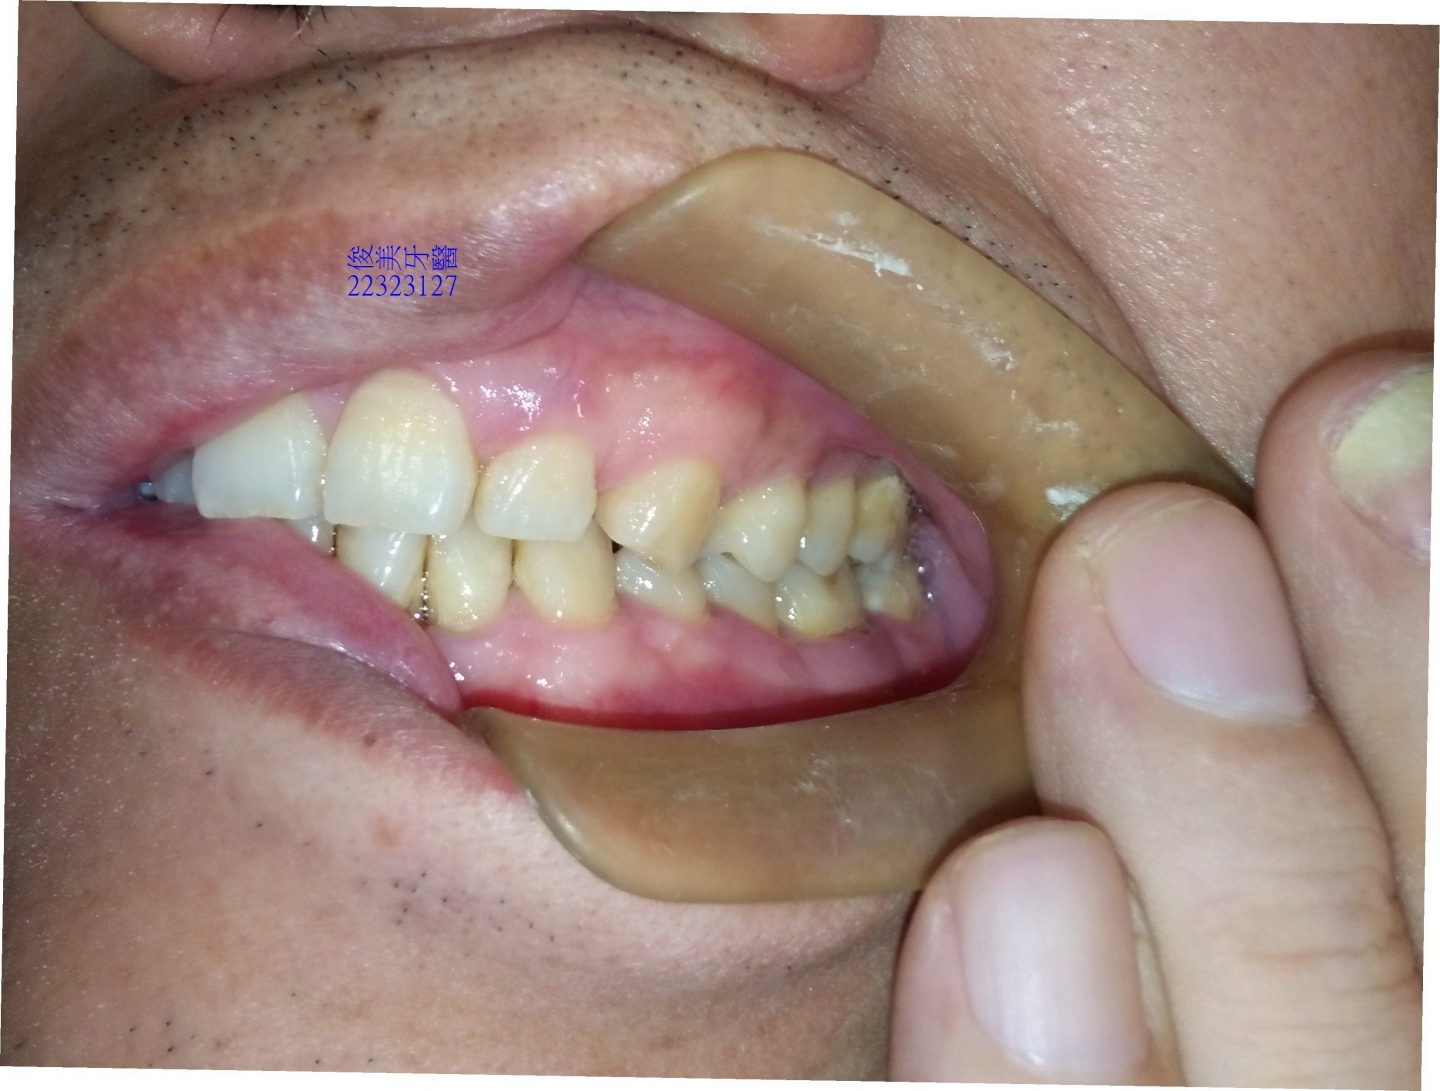

牙齒位移,前牙受力明顯過多,牙齒磨損的很平,牙齒變短、切端變厚。

牙縫開始變大。

後牙咬合高度逐漸變低。

後牙咬合高度逐漸變低;犬齒受力大,高度剩下2/3,切端皆已磨損喪失。